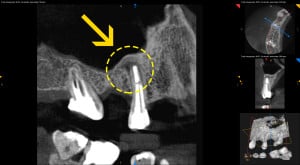

• Po wykonaniu tomografii volumetrycznej zęba 15 stwierdzono rozległą zmianę okołowierzchołkową.

• Wykonanie nowoczesnej diagnostyki pozwoliło na znacznie szybszą ocenę gojenia w stosunku do prześwietleń takich jak ortopantomogram lub radiowizjografia i skróciło okres obserwacji gojenia.